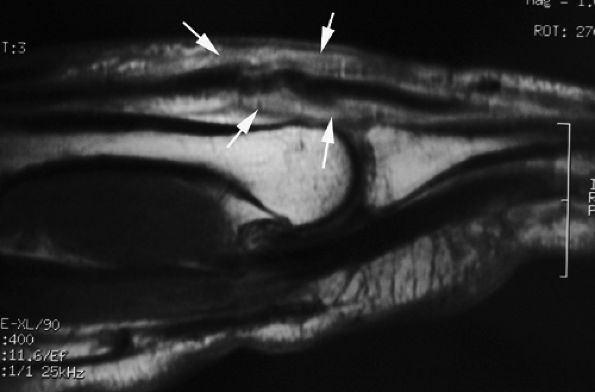

The UCL lies deep to the overlying low-signal adductor aponeurosis on coronal images (Figs. 11.7 and Fig. 11.8). In a nondisplaced partial or complete tear of the UCL, the ligament appears thickened all along its course, sometimes with a small gap. When displaced, the UCL appears as a proximally retracted round or stump-like structure, which demonstrates low signal on all sequences. It is no longer parallel to the long axis of the thumb and presents an increased horizontal orientation.

Stener's lesion may present with a “yo-yo on a string” pattern, with the retracted and balled-up UCL representing the yo-yo and the more distal linear adductor aponeurosis representing the string (Fig. 11.9).

On axial images, the ligament may be seen lying above or intersecting the adductor aponeurosis.